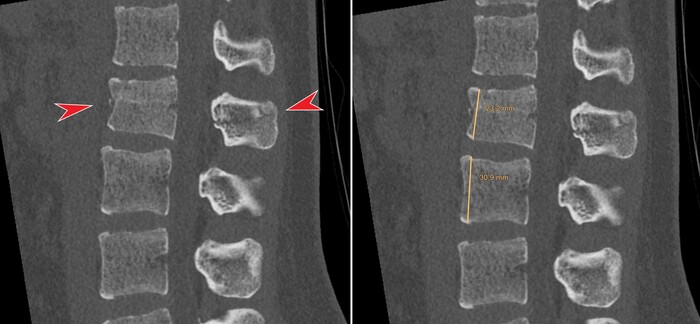

Тут позволю возразить: представленное выше - одно из встречающихся тяжёлых последствий черепно-мозговой травма, а именно т.н. ДАП или диффузное аксональное повреждение:

Диффузное аксональное повреждение (ДАП) - это тяжелая форма травматического повреждения головного мозга возникающая за счет воздействия сдвигающих сил. Диффузное аксональное повреждение потенциально трудно диагностировать, поскольку проявления при компьютерной томографии могут быть едва различимы, однако оно может приводить к тяжелым неврологическим нарушениям.

Диффузное аксональное повреждение является результатом воздействия сдвигающих сил возникающих при ротационном ускорении (реже торможении). Из-за разной плотности (относительная масса в единице объема) белого и серого вещества сдвиг происходит преимущественно в аксонах на границе серого и белого вещества, это и отражает название патологии. В большинстве случаев эти силы приводят и к повреждению клеток, что проявляется отеком. Но полный разрыв аксонов происходит только в тяжелых случаях.